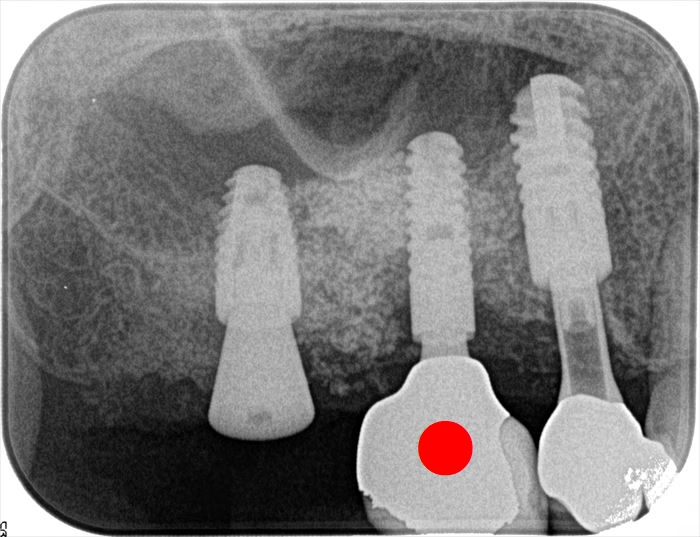

画像左端の右上第二大臼歯部分のインプラント埋入オペ時のデンタルレントゲン写真です。

丸印が本日撤去するインプラントです。

インプラントネック部分が骨吸収を起こしています。